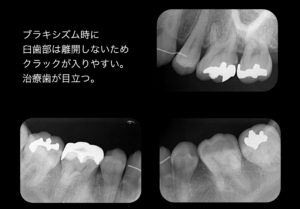

矯正専門医にて上下左右第一小臼歯抜歯による全顎的矯正治療を行う。

抜歯したスペースを埋めるために犬歯が内側に入りすぎて、下顎の左右の動きを制限してしまっていたと思われる。